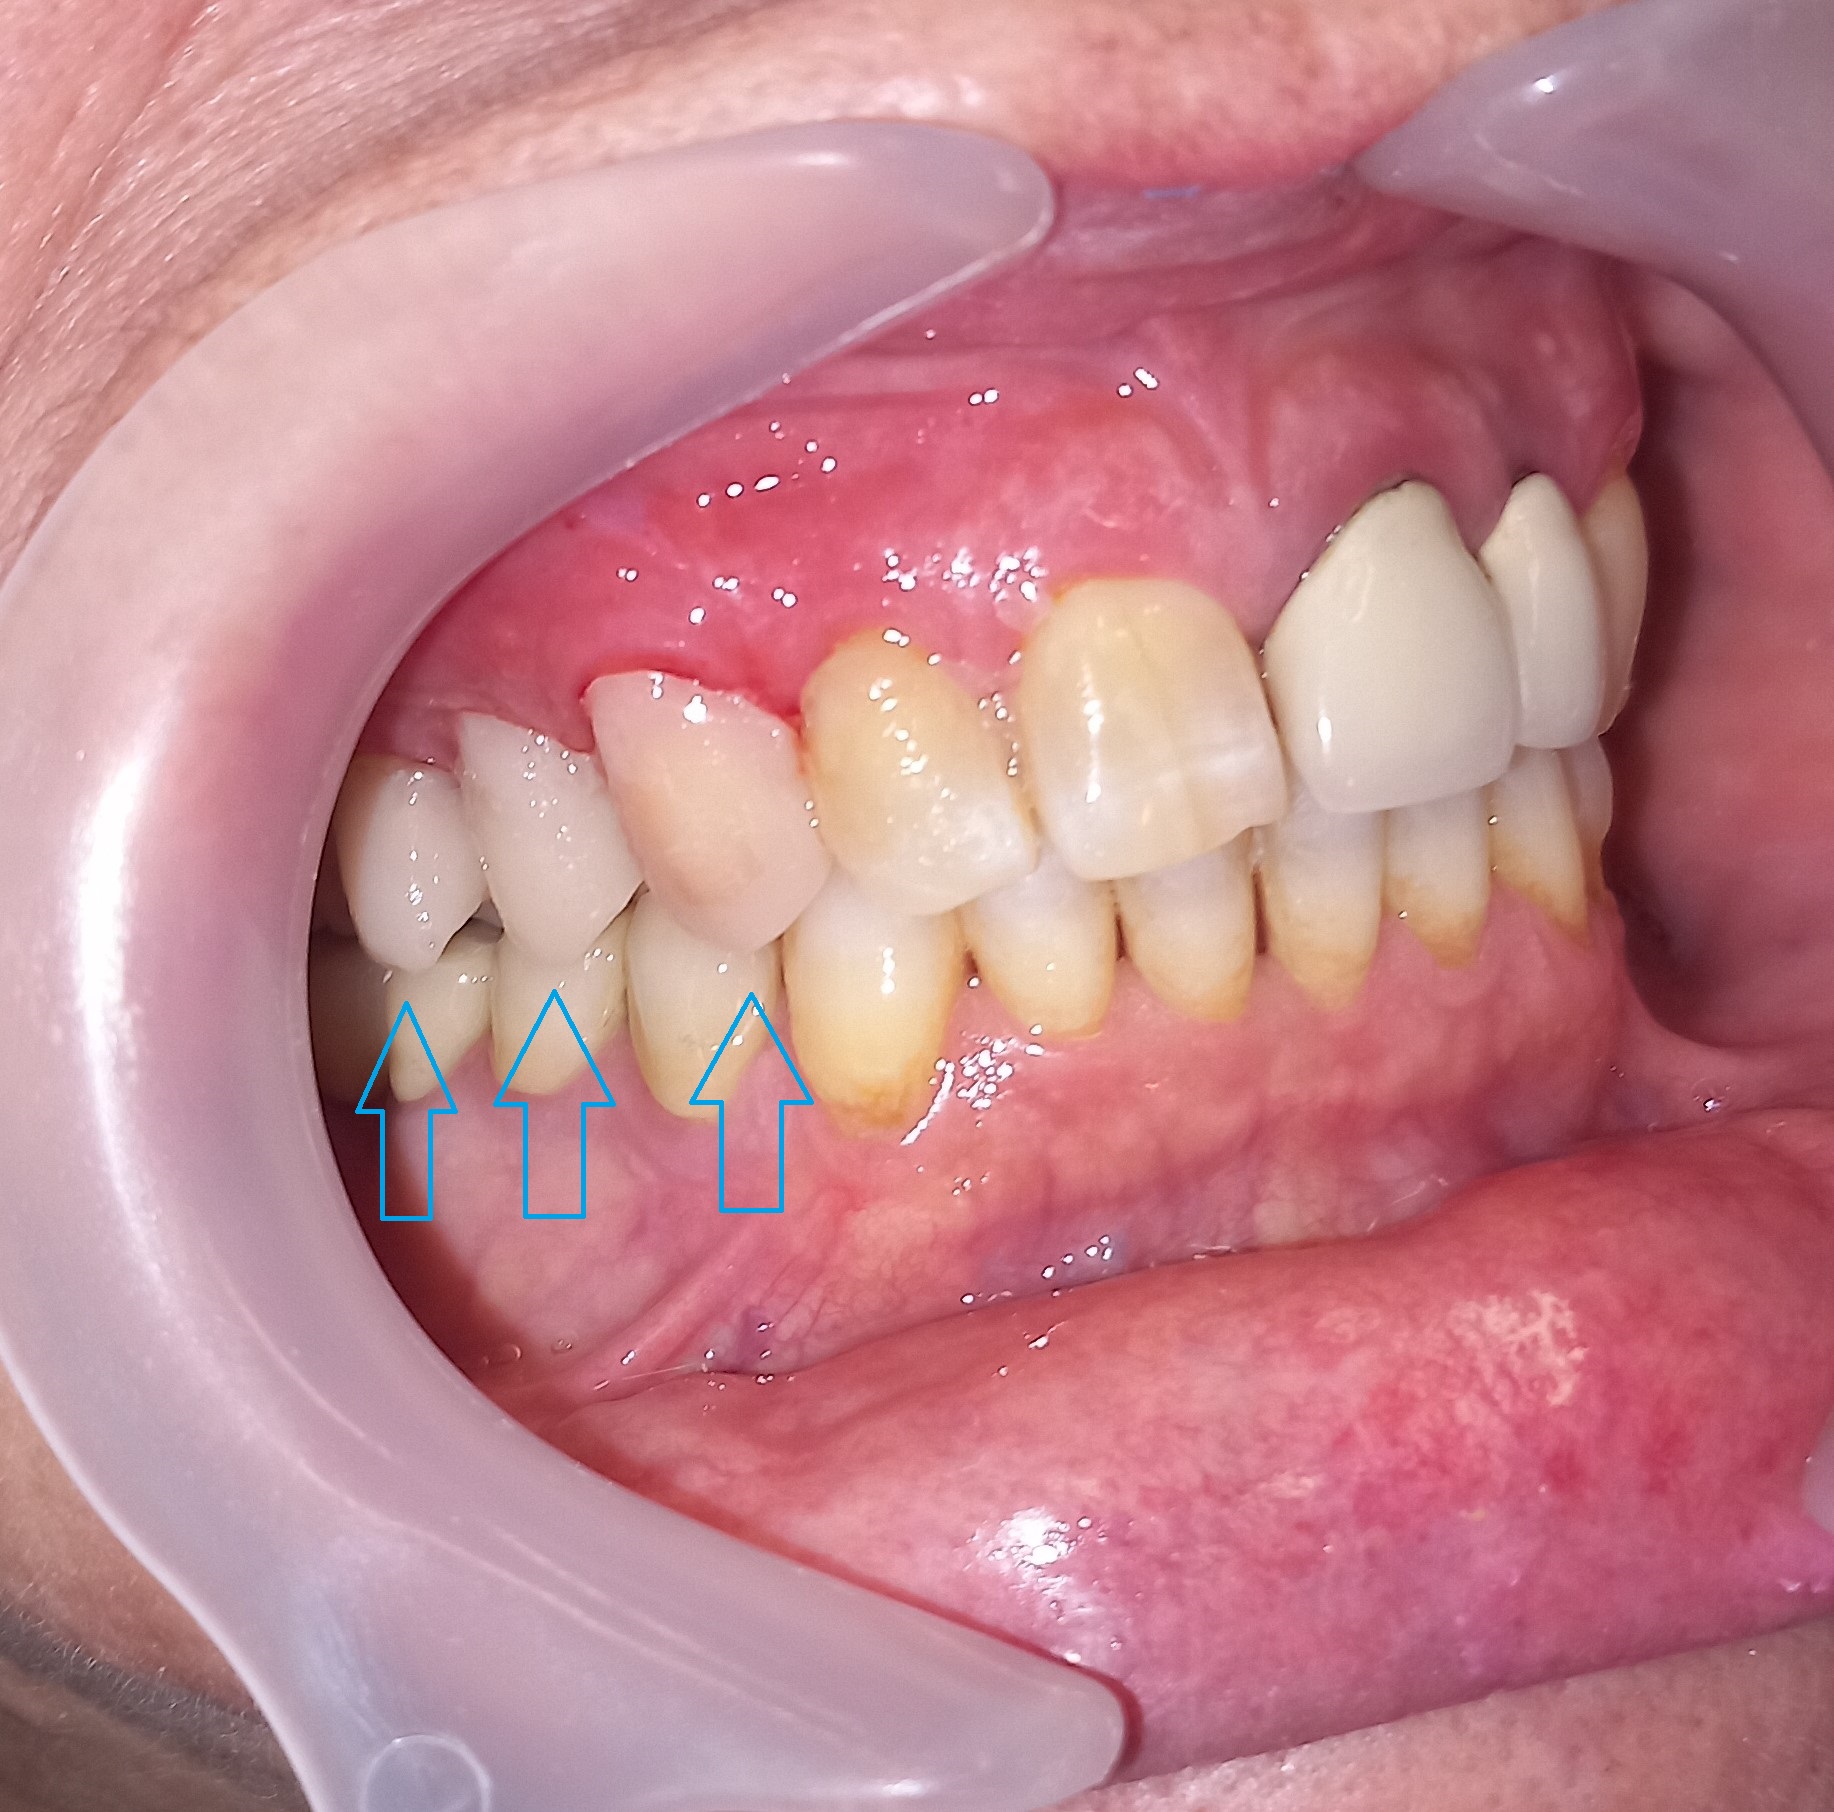

Αρχική εικόνα των δοντιών μετά την αφαίρεση της παλιάς γέφυρας

Τα δόντια μετά τις απαραίτητες απονευρώσεις και τις ανασυστάσεις

ΤΕΛΙΚΗ ΕΙΚΟΝΑ